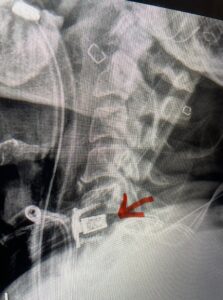

Another patient, a 77 year-old female, presents with pain, numbness, and weakness of her arms and difficulty with balance over a 6-month period. MRI revealed severe osteophytic disease at C5-C7 with cord compression (Fig. 4). Further work-up by fine-cut cervical CT to evaluate the nature of compression revealed a completely calcified osteophyte (Fig. 5). Although the patient had a good lordosis and a posterior cervical approach would accomplish an adequate decompression, we elected to perform a two-level anterior cervical discectomy and fusion. This particular osteophyte is formidable because of its size but the compression was all anterior and would be a less invasive approach. Fortunately, during the procedure, the patient had a fair amount of osteoporosis which allowed the osteophyte to be drilled and bit away with considerable ease. Interestingly, the C6 7 osteophyte which was more a sheet of osteophyte was more challenging to remove. In the end the decompression went well, and we placed two interbody devices filled with bone graft with plates at each level (Fig. 6). The patient had a nice recovery with immediate reduction of pain and numbness. This case demonstrates the importance of recognition of cervical myelopathy in its early stages. A significant reversal of function is generally the rule if the patient has appropriate correlative findings on exam and MRI, particularly with long tract distribution weakness development within a year time period.

Fig 5a: Sagittal and axial cervical fine-cut CT scan demonstrating severe osteophyte formation causing cord compression at C 56 (red arrow)

Fig 5b: Sagittal and axial cervical fine-cut CT scan demonstrating severe osteophyte formation causing cord compression at C 56 (red arrow)

Fig 6: Intraoperative lateral cervical x-ray demonstrating placement of interbody cages and plates